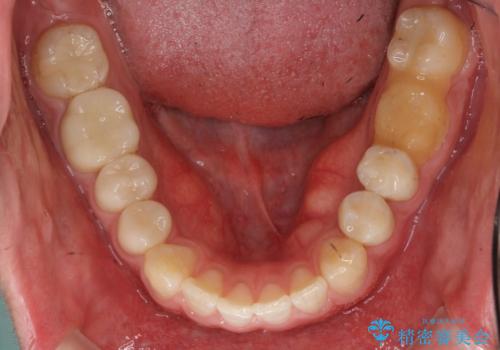

奥歯のかみあわせも問題なく、また、下の前歯のがたつきが元からない場合は上の部分矯正が十分可能です。

上下親知らずの抜歯や虫歯処置も矯正前後で行っています。